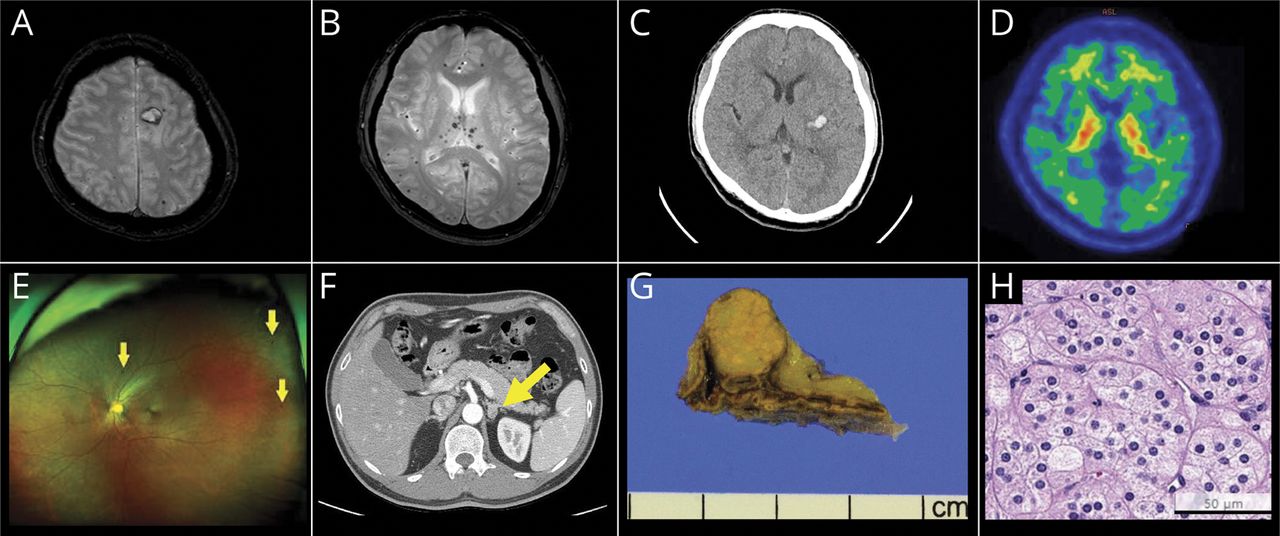

大脑核磁共振(A, B)。梯度回波t2加权成像显示了脑内出血(我)在左额叶优越,脑microbleeds (CMBs)结的白质和灰质,基底神经节和花托。(C)急性我左侧基底核是脑CT。(D)18F-flutemetamol淀粉样宠物没有显示出淀粉样蛋白沉积在大脑。(E)视网膜多点的出血(箭头)所示。(F)肾上腺CT显示了一个1.7厘米的质量在左肾上腺(箭头所指)。(G)肾上腺质量是1.3×1.3×1.3毫升和明确的。(H)肾上腺皮质腺瘤病理证实,基于微观发现:定义良好的细胞边界多边形粉红色细胞,清除细胞丰富,精致有液泡的细胞质,细胞核,是中央,圆,平淡(苏木精和伊红说,400×放大,酒吧= 50μm)。

一个47岁的男子来到大学附属医院神经病学门诊部。首页他抱怨种种困难和口齿不清,早上突然发生伴随头晕到访前17天,此后一直提高。他还作为一个计算机程序员工作。他过去有显著高血压病史(抗高血压药物3日)7年来,与负检查前一集的短暂的眩晕,并附带视网膜出血的病因不明。在他访问期间,他的血压(BP) 145毫米汞柱/ 95毫米汞柱。在美国国立卫生研究院卒中量表(署),他是得分1由于轻微的联接性失语。他的大脑MRI在同一天被任命和显示急性颅内出血1.7厘米(我)在左优越的额叶我得分为0 (图,一个)。MRI显示> 200 CMBs灰质和白质的路口,基底神经节、脑桥、小脑梯度回波t2加权成像(图B)。此外,3可见,白质hyperintensities(法泽卡斯等级2)检测在t2加权成像。他指示继续服用抗高血压药物。

第二天,病人参观了急诊科突发进行性加重,发生在午夜,1小时前访急诊室。BP是170/115毫米汞柱。他提醒和关注,但显示右胳膊和腿软弱除了轻微的联接性失语署(3)。他的脑部CT扫描显示一个新的急性我我评分(0)在左侧基底节(图中,C)。他承认我的保守管理病房。

在病人的10天承认,他的神经体征改善只有联接失语症仍然在署(1),但他的方案是uptitrated包括4日抗高血压药物。他的血液测试显示低水平的血清钾(3.5更易/ L在入学的第一天,3.0更易/ L的第四天承认[正常范围3.5 - -5.1更易/ L]);然而,他没有显示相关症状或体征。NOTCH3基因测试没有发现任何致病/可能致病变种。他的APOE基因型是ε2 /ε3。18F-flutemetamol淀粉样宠物进行排除联合创新艺人经纪公司的可能性。结果显示没有证据表明大脑淀粉样沉积(图D)。出院后随访3周,24小时动态BP监控显示,他的血压110 - 130毫米汞柱。因此,他的抗高血压药物会被修改,以包括3了。出现第二个我,三个月后,他重新回到了工作岗位。

六个月后病人的我,后续测试显示低钾血清电解质水平(2.7更易/ L)。因此,他建议停止服用利尿剂在抗高血压药物1月。然而,钾水平仍低(2.8更易/ L)。他补充口服氯化钾。中断利尿后,他的英国石油公司是113/83毫米汞柱。因此,考虑到他与众多CMBs伴随着2我在一个18天,原因不明的视网膜出血(图E),持续低血清钾、继发性高血压被怀疑。随后,荷尔蒙测试是由8我,结果如下(括号内的正常范围):血清醛固酮30.31毫微克/分升(仰卧位,4.1 - -20.8 ng / dL)和血浆肾素活性≤0.20 ng / mL / h (0.5 -1.9 ng / mL / h)。血清醛固酮的比例(ng / dL)血浆肾素活性(ng / ml / h)超过20,这表明可能的PA。盐水加载测试进行确认。后静脉注射生理盐水的2 L 4小时,血清醛固酮水平为45.87毫微克/分升和不减少< 5毫微克/分升,这证实了PA。肾上腺CT (图F)显示一个1.7厘米左肾上腺。肾上腺的质量,通过腹腔镜肾上腺切除术,是1.3×1.3×1.3厘米3、定义良好的肾上腺皮质腺瘤(图中,G和H)。手术治疗后,病人的英国石油公司控制只有1抗高血压药物。他被诊断为继发性高血压由于肾上腺皮质adenoma-related PA。